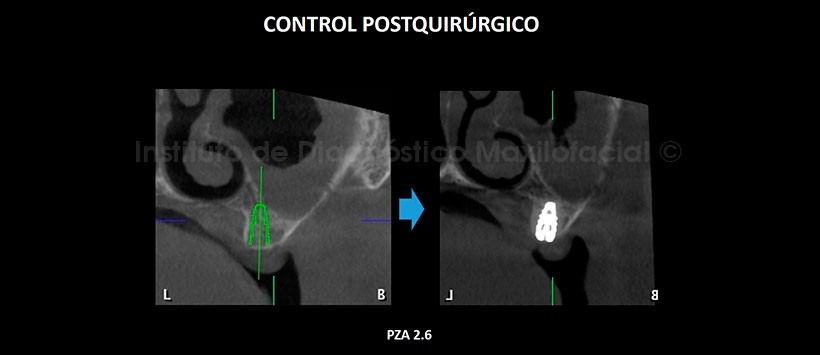

En la tomografía computarizada de haz cónico (TCHC), se realiza la planificación virtual de colocación de cuatro implantes dentales en zonas de piezas 17, 23, 26 y 27 (Figura 2, 3), y sobre la planificación se realiza la confección virtual de la guía quirúrgica (Figura 4). En la reconstrucción 3D (Figuras 5) se aprecia con detalle la orientación y la disposición final de los implantes dentales a ser colocados, además se observa la guía quirúrgica confeccionada virtualmente que posteriormente fue impresa físicamente para su utilización en el procedimiento quirúrgico (Figura 6).

En la tomografía de control post quirúrgico (Figura 7, 8, 9, 10 y 11), se aprecia los implantes con estructura ósea circundante, en las posiciones donde fueron planificadas virtualmente.